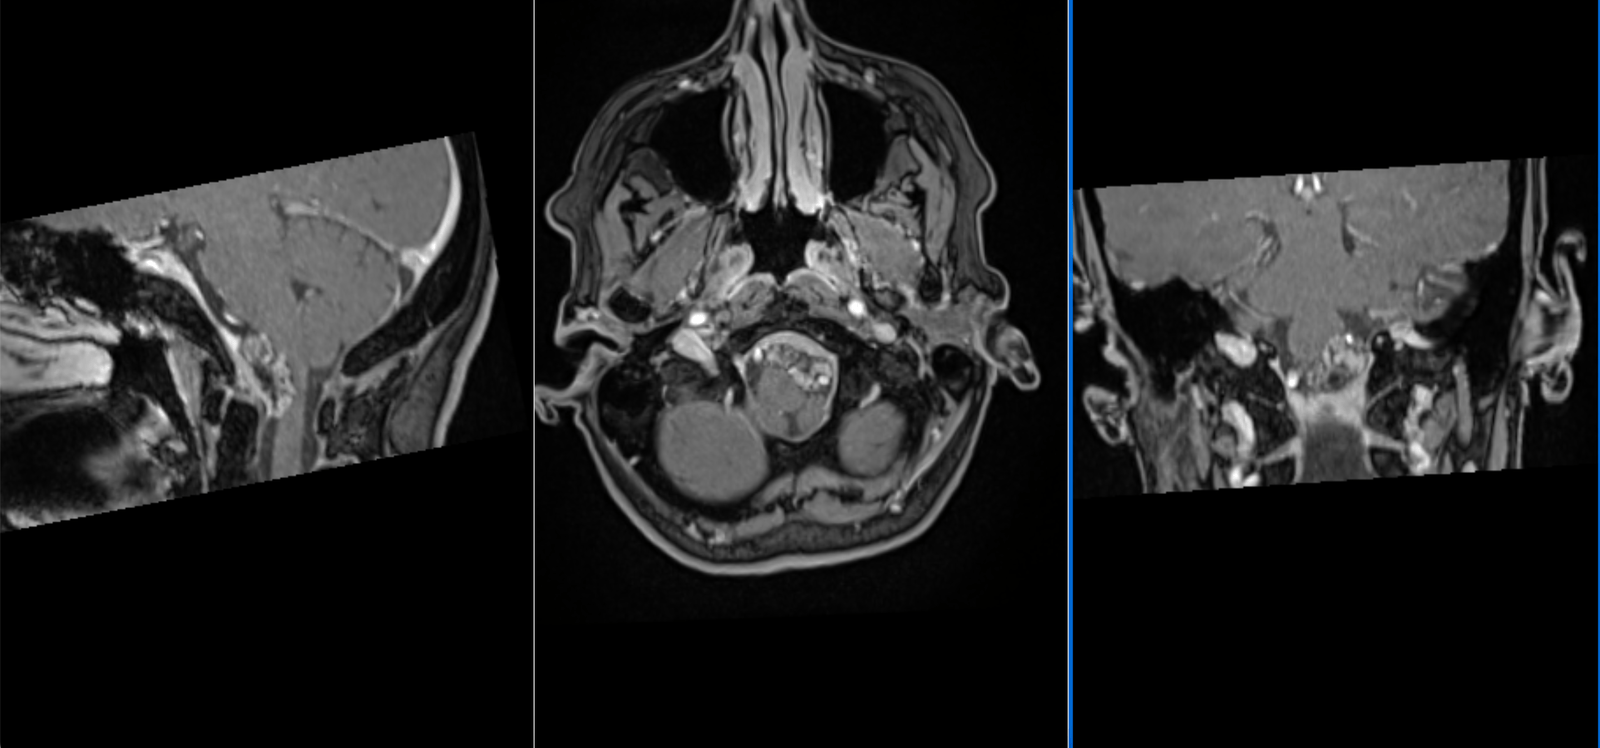

Vă prezentăm cazul unui pacient diagnosticat cu meningiom de aripă de sfenoid dreaptă, o tumoră cerebrală benignă care se dezvoltă...